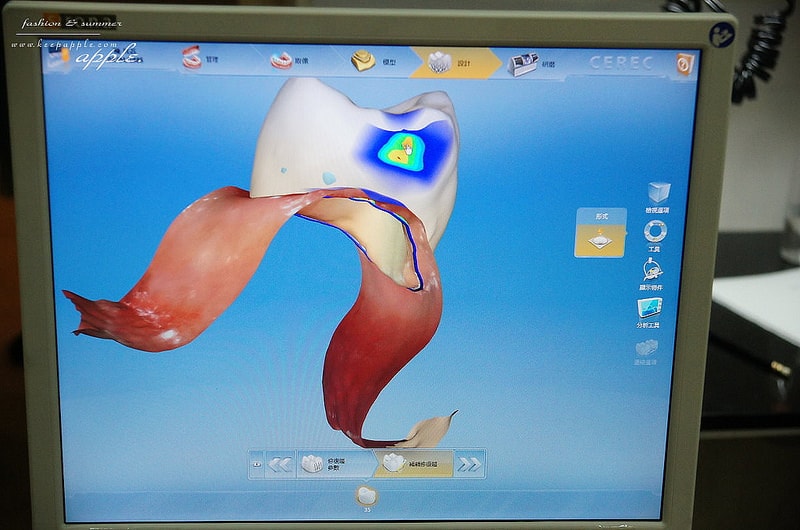

我選的材質是很好的玻璃陶瓷

而且因為是三色的設計仿真度很高

然後就是用超專業的比色儀比對牙齒與假牙的顏色

比對越細,出來的牙齒顏色越接近原本的齒色

看起來更自然~

然後會再由牙技師進行更細緻的上色

上完色後會再進行超高溫烤爐烘烤定色